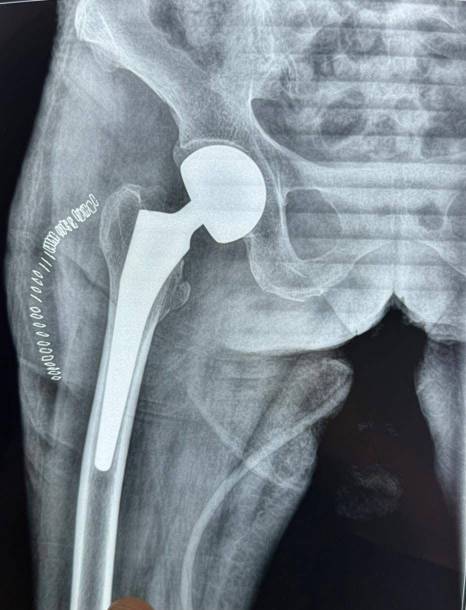

نجاح عملية لمريضة تبلغ من العمر 105 أعوام بمدينة الصدر الطبية في النجف

أجرى فريق طبي في مدينة الصدر الطبية التابعة لدائرة صحة النجف الأشرف عملية نوعية لمريضة تبلغ من العمر 105 أعوام، كانت تعاني من كسر في عنق الفخذ، وهو من الإصابات الشائعة والخطرة في هذا العمر المتقدم.

وأكدت إدارة المدينة الطبية أن الفحوصات المختبرية والشعاعية في بيان :" أظهرت وجود ضعف شديد في عضلة القلب لدى المريضة، ما جعل العملية معقدة للغاية، خصوصاً فيما يتعلق بالتخدير والتعامل مع الحالة الصحية الدقيقة.

وأضافت الإدارة:" أن الفريق الطبي تمكن بفضل خبرته ومهارته من إنجاز العملية بنجاح، وتماثلت المريضة للشفاء بعد خروجها من غرفة العمليات وهي بحالة صحية مستقرة، وذلك بجهود الفريق الطبي والتمريضي وكادر التخدير والكوادر الصحية المساندة في المدينة الطبية ./ انتهى